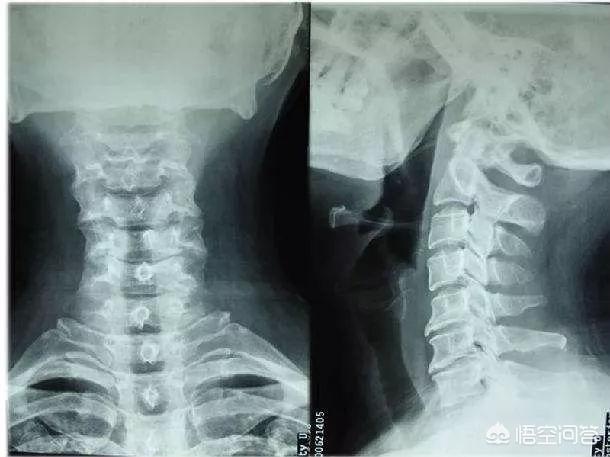

La pression scolaire sur nos enfants est très élevée, ce qui est mieux connu dans le monde entier, et si cet enfant est au collège ou au lycée, je soupçonne qu'il a une lésion grave dans sa colonne vertébrale, et ces points focaux continueront à presser et à irriter les nerfs, ce qui conduit à des troubles des nerfs, et la raison pour laquelle les patients ont des difficultés à détecter les organismes n'est pas parce qu'ils ne les ont pas, mais parce qu'ils ne les ont pas vérifiés au bon endroit, et les douleurs thoraciques ne sont pas toujours un problème cardiaque, les maux de tête ne sont parfois pas un problème de tête.

Je suggère aux parents d'emmener leurs enfants à l'hôpital pour les examiner : IRM du cou et du thorax et clichés ortho-latéraux, qui peuvent révéler quelque chose de nouveau, et le traitement est mieux de traiter la cause, jamais à l'aveuglette.